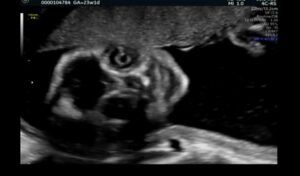

白黒でコントラストが強く、輪郭がぼやけがちなエコー写真。

カメラ目線のエコー写真

投稿されたのは、妊娠25週の頃に撮影されたエコー写真と、生後7日の可愛らしい赤ちゃんの写真2枚。エコーには、こちらをぎょろりと見つめ、ニヤリと笑っているようなちょっと怖い表情が写っていました。

初めての妊娠だったYukiさんは、この写真を見たとき「こんなものなのかな?」とも思いつつ、夫婦2人で「めっちゃこっち見てるね。ホラーだね」と笑い合っていたそうです。

その後、他の人が「これよりホラーなエコーありますか?」と妊娠中のエコー写真を投稿しているのを見かけ、自分のエコーもかなりホラーだったことを思い出してリプライ。すると「優勝です」「夢に出そう」といったコメントが多数寄せられたのだとか。